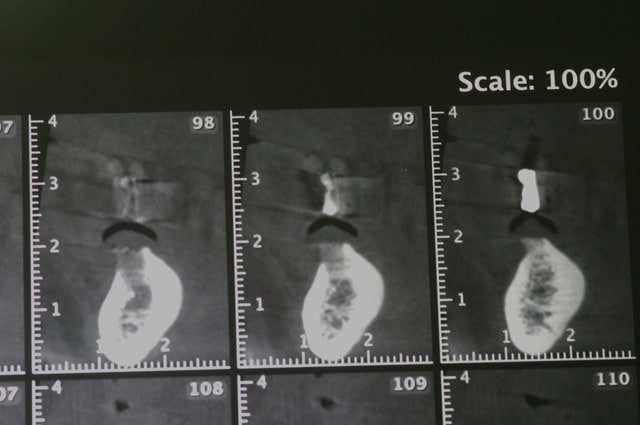

voici quelques images (de mauvaises qualités..désolé) d'un cone beam.

à la base le plan de traitement consistait en la pose de cinq implants et d'un bridge sur pilotis. mais dans le secteur mandibulaire gauche, il me semble que le NDI montre une anatomie un peu bizare. c'est mes yeux ou bien...?